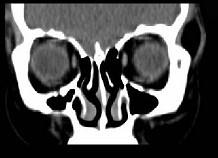

问题 女,31岁,在左眶外上缘发现一包块,质软,余所见无明显异常。如图所示病灶应诊断为 ( )

选项 A、表皮样囊肿 B、淋巴管瘤 C、错构瘤 D、脂肪瘤 E、畸胎瘤

答案 D